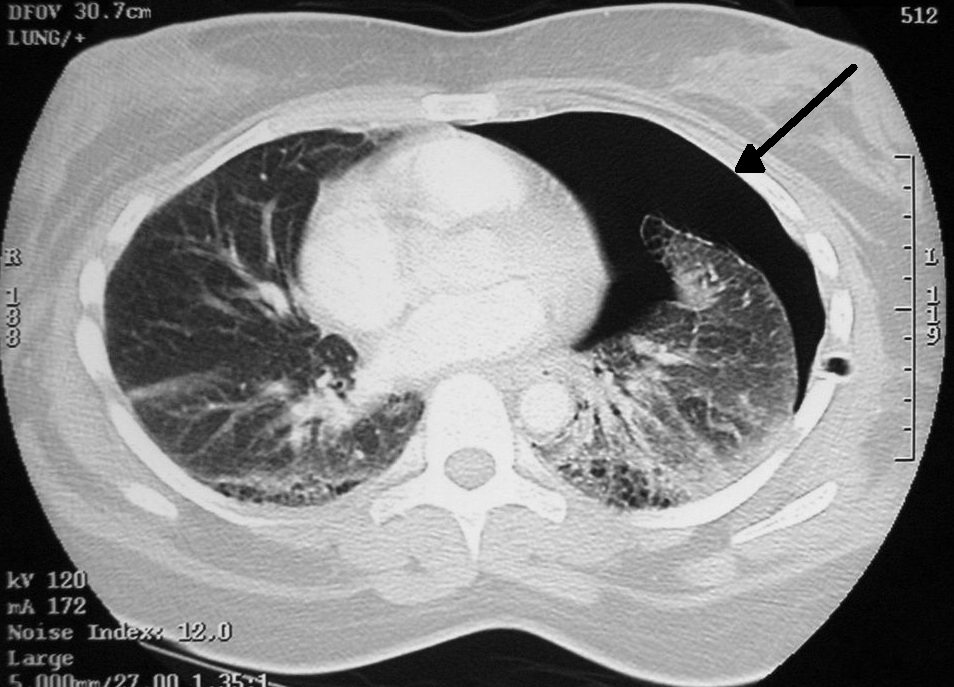

- Для диагностики небольших по размеру пневмотораксов КТ является более надёжным методом по сравнению с рентгенографией.

- Для дифференциального диагноза больших эмфизематозных булл и пневмоторакса наиболее чувствительным методом является КТ.

- КТ показана для выяснения причины вторичного спонтанного пневмоторакса (буллёзная эмфизема, кисты, интерстициальные болезни лёгких и др.).